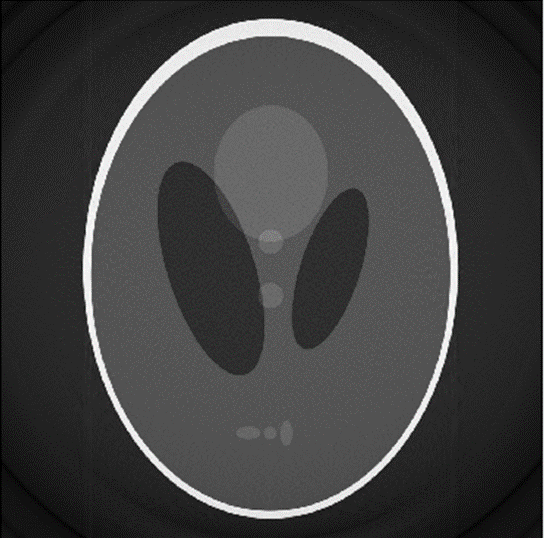

Figure 8: reconstruction from the sinogram in figure 8

The reconstructed image is sharper with more of the finer details showing through. Although within the image there still is some noise as well as a lack of contrast. The reconstruction also has the same circle around it as the non-filtered reconstruction.

Figure 8: reconstruction from the sinogram in figure 8

The reconstructed image is sharper with more of the finer details showing through. Although within the image there still is some noise as well as a lack of contrast. The reconstruction also has the same circle around it as the non-filtered reconstruction.

Analysis

Comparing the reconstructions of the images as seen in Figure 5 and Figure 8, the filtered back projection creates a clearer image than the non-filter one. The reasoning for this almost bloom effect on the non-filtered image is the polar sampling in the Fourier slice theorem. This polar sampling causes the bloom effect as there are more samples near the center in Fourier space. These samples near the center correspond to low frequencies, so during the back filtering more lower frequencies samples are captured. This difference in the number of low frequencies captured compared to high frequencies causes most of the details in the image to be lost. These details get lost as these details tend to reside mostly within the higher frequencies in Fourier space. The filter image also shows a noise within the image. This is because the filter that was used is a ramp filter. This type of filter disproportionally amplifies the higher frequency in Fourier space. Although in this case where the higher frequency were the ones that were sample less, the effect is less noticeable. However, this noise could be reduced by using a higher order filter rather than this basic ramp filter. There are also circles that appear around both filtered and non-filtered reconstruction. These circles are more than likely to come from the forward projection stage when the image matrix is rotated. This would occur as during this stage the forward projected image is resampled as well as receiving some interpolation.